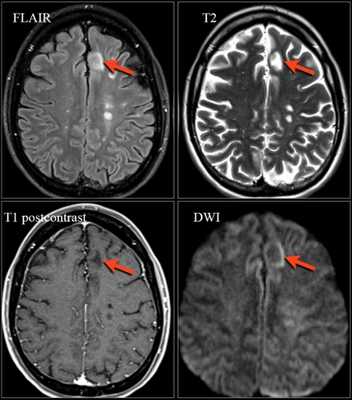

Лучшей методикой выявления лакунарных инфарктов и лейкоареоза является МРТ в режиме Т2-ВИ (особенно в варианте последовательности с подавлением сигнала от ликвора - FLAIR). Свежие лакунарные инфаркты можно дифференцировать от старых на основании ДВИ: в первом случае коэффициент диффузии снижен, во втором - не изменен или повышен. Кроме того, очаги лакунарных инфарктов в хронической стадии не накапливают контрастное вещество. При МР-спектроскопии у пожилых больных с артериальной гипертензией отношение содержания миоинозитола к креатинину выше, чем в контрольной группе (примерно такое же, как у пациентов с болезнью Альцгеймера). При гипертонической и артериосклеротической энцефалопатиях ультразвуковое исследование интракраниальных артерий выявляет повышенное сосудистое сопротивление в бассейнах среднемозговых артерий, причем степень его повышения коррелирует с тяжестью артериальной гипертензии.

Хроническая ишемия и дисфункция головного мозга (вплоть до развития сосудистой деменции) часто сочетаются с крупноочаговыми нарушениями мозгового кровообращения по ишемическому или геморрагическому типу в хронической стадии. Характерным диагностическим признаком ишемического инсульта в хронической стадии является утрата части объема вещества головного мозга с признаками глиоза по краю зоны поражения. Инфаркт мозга может возникать в бассейне крупной мозговой артерии либо на границе зон кровоснабжения двух сосудистых бассейнов (последнее характерно для инсультов, связанных с нарушениями гемодинамики, а не тромбоэмболическими осложнениями). Размеры и форма области поражения варьируют в широких пределах; в классическом случае зона энцефаломаляции при хроническом инсульте имеет клиновидную форму (При КТ эти очаги видны как четко очерченные зоны пониженной плотности, желудочек на стороне поражения расширяется, а борозды углубляются. Накопления контрастного препарата не наблюдается; при КТ-ангиографии может выявляться снижение кровотока в пораженном сосуде или его окклюзия; перфузия в этой зоне отсутствует или значительно снижена).